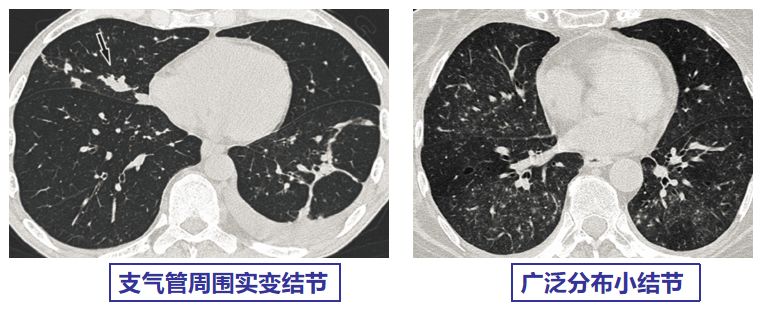

CMV肺炎的影像学可表现为以下几种:

小叶中央性结节、随机或淋巴管周围分布结节、广泛磨玻璃影、气腔实变、叶间隔增厚。其中小叶中央性结节 (69%)、双肺GGO(69%)、气腔实变(54%)最为常见。

【图4】文献报道的巨细胞病毒肺炎常见影像表现